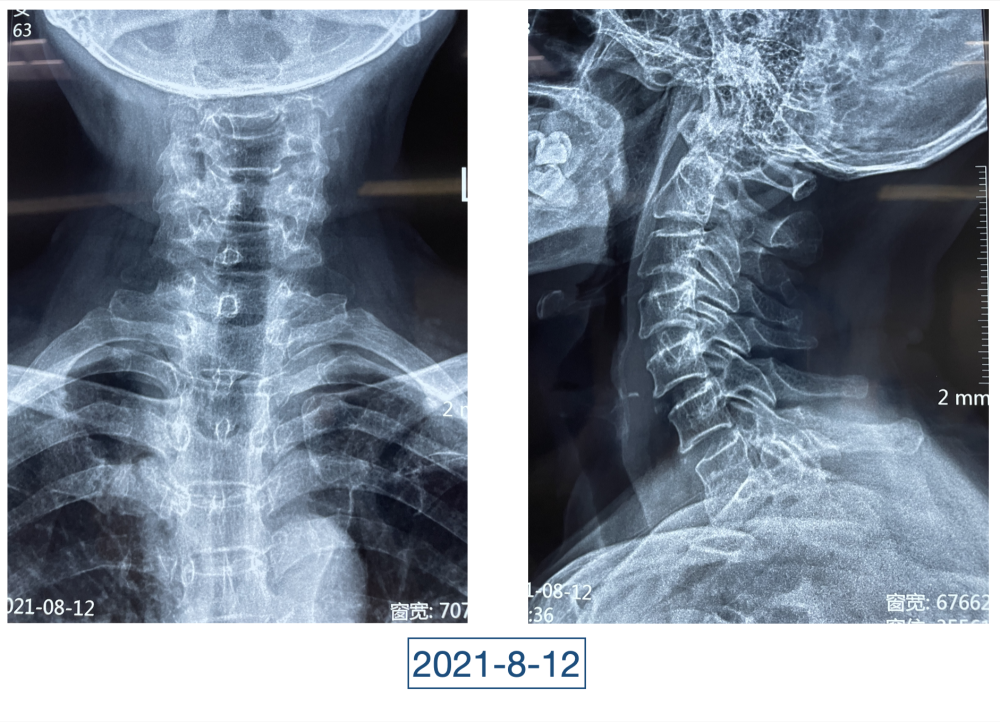

“虽说没到奄奄一息的地步,但一看就是患了大病,整个人都瘦脱相了。”李辉是西安市红会医院关节病医院病区副主任,2020年4月初第一次见到黄大娘时,他吓了一跳。黄大娘今年61岁,2019年腊月二十九,在家打扫卫生准备迎接新年的她突然开始高烧不退,腰背也痛。连夜送到当地医院补液、止疼、退烧、抗感染,一套组合拳下来烧是退了,疼痛的症状却持续在加重。从过年到正月,一直在当地医院输液、打针,黄大娘都没有好转,疼痛的地方反而越来越多。大概过半月,就多一个地方,腰、背、胸、颈部、关节、脚……此起彼伏,全身上下都觉得疼痛无比。哪里疼就去哪个科,今年四月前,黄大娘辗转多家医院多个科室寻求治疗,住院出院了一次又一次,连最高级别的抗生素都用到了,但就是没有效果。

全身上下11处骨关节被破坏!密密麻麻的诊断看得李辉毫无思绪,这么久都查不出来的病因能让他查出来吗?一时间,他也说不出话。看着黄大娘深深凹陷的双眼,浑身上下几乎看不见肉,就像罩着一层饥饿的青黄色的薄皮。过了好一会儿,他叹了口气,说:“先住下吧,用药把关节疼痛缓解一下,再想办法。”

近日随访得知黄大娘身体好转,李辉脸上的笑容掩饰不住,他说,据查阅文献,11处感染灶,这是全世界感染灶最多的骨关节感染,但现在,这罕见、复杂的病已经被治愈。